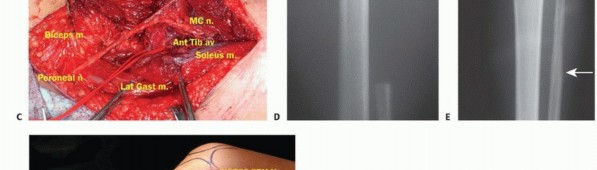

تشريح الشظية القريبة

تُعد الشظية القريبة (الرأس والجزء العلوي من العظم) موقعًا رئيسيًا لالتصاق الرباط الجانبي الوحشي (LCL) ووتر العضلة ذات الرأسين الفخذية. هذه الروابط ضرورية لاستقرار مفصل الركبة الجانبي. الأهم من ذلك، أن العصب الشظوي المشترك يلتف حول قاعدة رأس الشظية ليدخل نفق العضلة الشظوية الطويلة، مما يجعله عرضة للإصابة أثناء جراحة الأورام في هذه المنطقة.

الاستئصال من النوع الثاني (Type II Resection):

- الإشارة: يُستخدم لعلاج الأورام الغرنية عالية الدرجة، والتي عادةً ما يكون لديها تدمير قشري كبير مع امتداد خارج العظم.

- الإجراء: يشمل إزالة الشظية القريبة والمفصل الظنبوبي الشظوي، والحجرات العضلية الأمامية والجانبية، والعصب الشظوي، والشريان الظنبوبي الأمامي بشكل كامل. يتطلب هذا النوع ربط الشريان الظنبوبي الأمامي وقد يتطلب أيضًا التضحية بالشريان الشظوي.

- الحفاظ: لا يتم الحفاظ على العصب الشظوي والشريان الظنبوبي الأمامي.

وضعية المريض

يُستخدم وضع شبه الاستلقاء (رفع الجانب الذي سيتم إجراء الجراحة عليه بزاوية 45 درجة) للسماح بالوصول السهل إلى الحجرات الأمامية والجانبية، وكذلك للسماح بتشريح المساحة المأبضية. يتم تضمين الطرف بأكمله، من الرباط الأربي إلى القدم، في الحقل المعقم. هذا يسمح بتقييم نبضات القدم البعيدة وتنفيذ بتر فوق الركبة إذا لزم الأمر، على الرغم من أن هذا نادر الحدوث بفضل التقنيات الحديثة.

الشق الجراحي (القطع الجراحي)

يُستخدم "الشق الشظوي النفعي" (utilitarian fibular incision)، والذي يسمح بكشف واستئصال الأورام في جميع مستويات الشظية. يمتد هذا الشق من العضلة ذات الرأسين فوق مفصل الركبة، فوق الجزء الأوسط من الشظية، إلى الأمام باتجاه قمة الظنبوب، ثم ينحني خلفيًا وبعيدًا إلى الكاحل. يسمح هذا بتطوير سدائل جلدية عضلية أمامية وخلفية كبيرة.